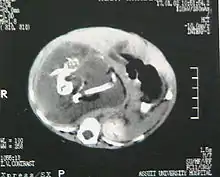

جنين داخل الجنين (بالإنجليزية: Fetus in fetu) هو عيب خلقي فيه تتكون كتلة من الأنسجة تشبه الجنين داخل الجسم. وقد وصف جورج وليام يونغ مثالا لهذه الظاهرة في عام 1808.[1]

هناك نوعان من نظريات المنشأ بشأن "الجنين داخل الجنين". نظرية تعتبر أن الكتلة تبدأ كجنين طبيعي ولكنه أصبح مغلف داخل توأمه.[2] والنظرية الأخرى تعتبر أن الكتلة هي ورم مسخي متطور للغاية. يحدث "الجنين داخل الجنين" بنسبة 1 لكل 500,000 ولادة حية.[3]

يمكن اعتبار الجنين داخل الجنين على قيد الحياة، ولكن فقط بمعنى أن الأنسجة المكونة له لم تمُت بعد أو لم يتم القضاء عليها. ومن ثَم، فإن حياة الجنين داخل الجنين هي أقرب إلى الورم حيث أن خلاياه لا تزال قابلة للحياة عن طريق النشاط الأيضي العادي. وعلى الرغم من عدم توافر ظروف الحمل في الرحم والسلى والمشيمة، فإنه يستطيع أن يتطور إلى ورم مسخي متميز بشكل خاص في أحسن الأحوال، أو إلى سرطانة مسخية منبثة في أسواء الأحوال. ومن حيث النضج البدني، فإن أعضاءه لديها إمدادات من الدم من المضيف، ولكن جميع حالات الجنين داخل الجنين لديها عيوب حرجة، مثل عدم وجود دماغ وظيفي أو قلب أو رئتين أو جهاز هضمي أو مسالك بولية. وفقا لذلك، في حين أن الجنين داخل الجنين يمكن أن يتشارك في خصائص شكلية معينة مع الجنين العادي، فإنه ليس لديه احتمال لأي حياة خارج التوأم المضيف. وعلاوة على ذلك، فإنه يشكل تهديدات واضحة لحياة التوأم المضيف الذي تعتمد عليه حياته الخاصة.[4]